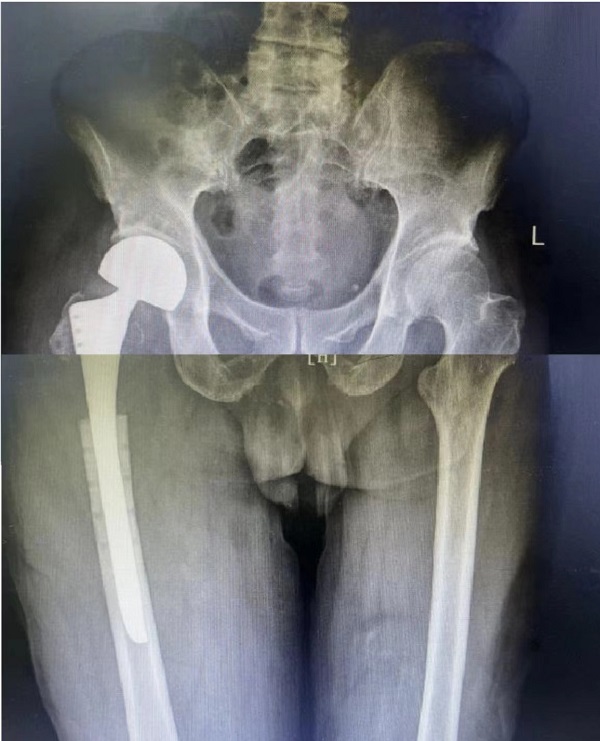

退休李师傅今年79岁,4个月前因右侧股骨近端病理性骨折在外院行瘤体切除,钢板内固定手术。近期下地活动时轻微扭伤后感右大腿根部疼痛伴活动受限,来二一五医院拍片提示:右股骨近端骨折术后再骨折伴内固定断裂。老年患者的股骨近端骨折若不积极正规治疗,可能因长期卧床引起肺部感染、泌尿系感染、深静脉血栓、褥疮等并发症,被称为“人生的最后一次骨折”。

创伤骨科郭永良主任、王争刚主任医师仔细了解患者病史、查体阅片,和患者家属多次沟通,阐明各种治疗方案的优缺点,最终决定行右股骨近端内固定钢板及骨水泥取出、人工股骨头置换术。手术由郭永良主任亲自主刀、在王争刚主任医师等辅助下进行,历时1.5小时顺利完成。现术后3周,患者髋关节功能恢复良好,可扶拐下地活动。